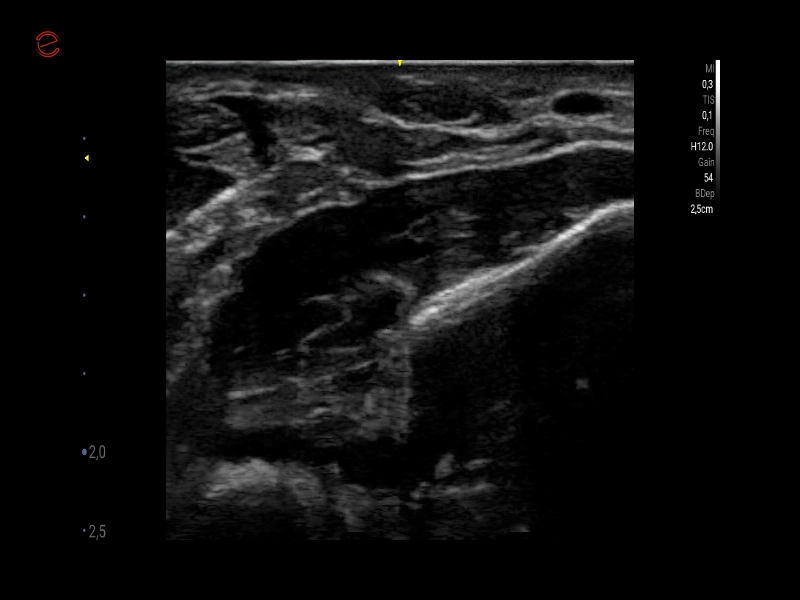

MyLab™9 Platform - Very-superficial linear imaging with Power Doppler algorithm

MyLab™9 Platform - Very-superficial linear imaging with Power Doppler algorithm